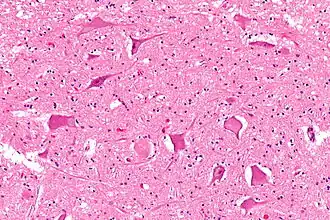

Central chromatolysis

Central chromatolysis is a histopathologic change seen in the cell body of a neuron, where the chromatin and cell nucleus are pushed to the cell periphery, in response to axonal injury.[1][2] This response is associated with increased protein synthesis to accommodate for axonal sprouting. In addition to traumatic injuries, central chromatolysis may be caused by vitamin deficiency (pellagra[3]).